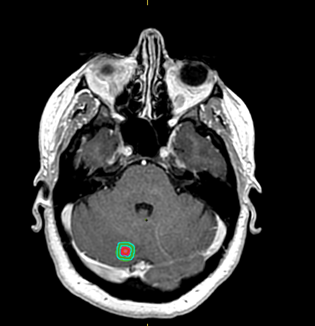

Stéréotaxie

La radiothérapie stéréotaxique est une forme de radiothérapie de très haute précision qui permet d’irradier à haute dose de petits volumes en un nombre limité de séance.

Centre de référence en stéréotaxie en Normandie, nous proposons toutes les techniques de radiothérapie stéréotaxique : cérébrale, pulmonaire, osseuse, ganglionnaire, hépatique, prostatique.